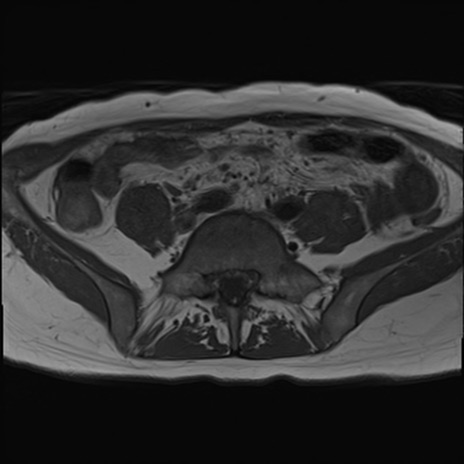

症例39 T1WI(横断像)

MRI(4日後)